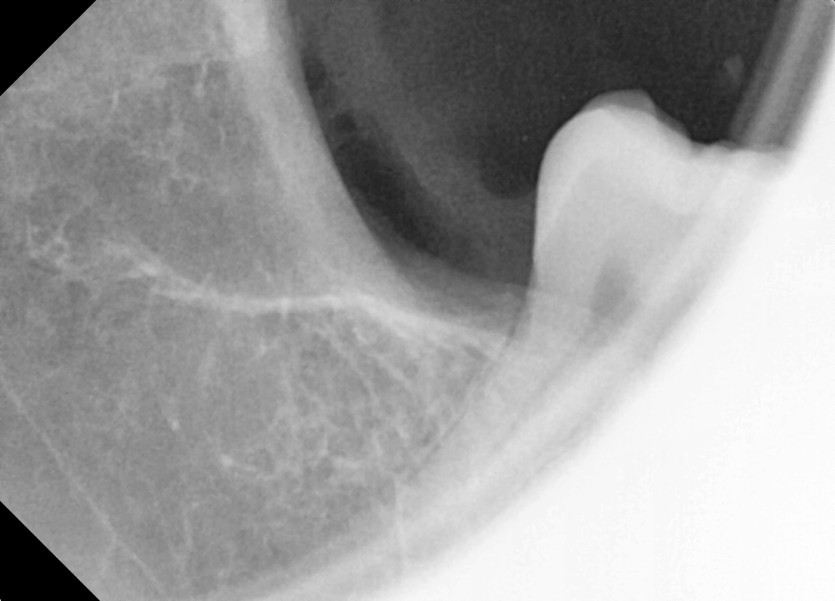

#38,48 사랑니 발치

구강 외과 전문의가 당일 발치했습니다.